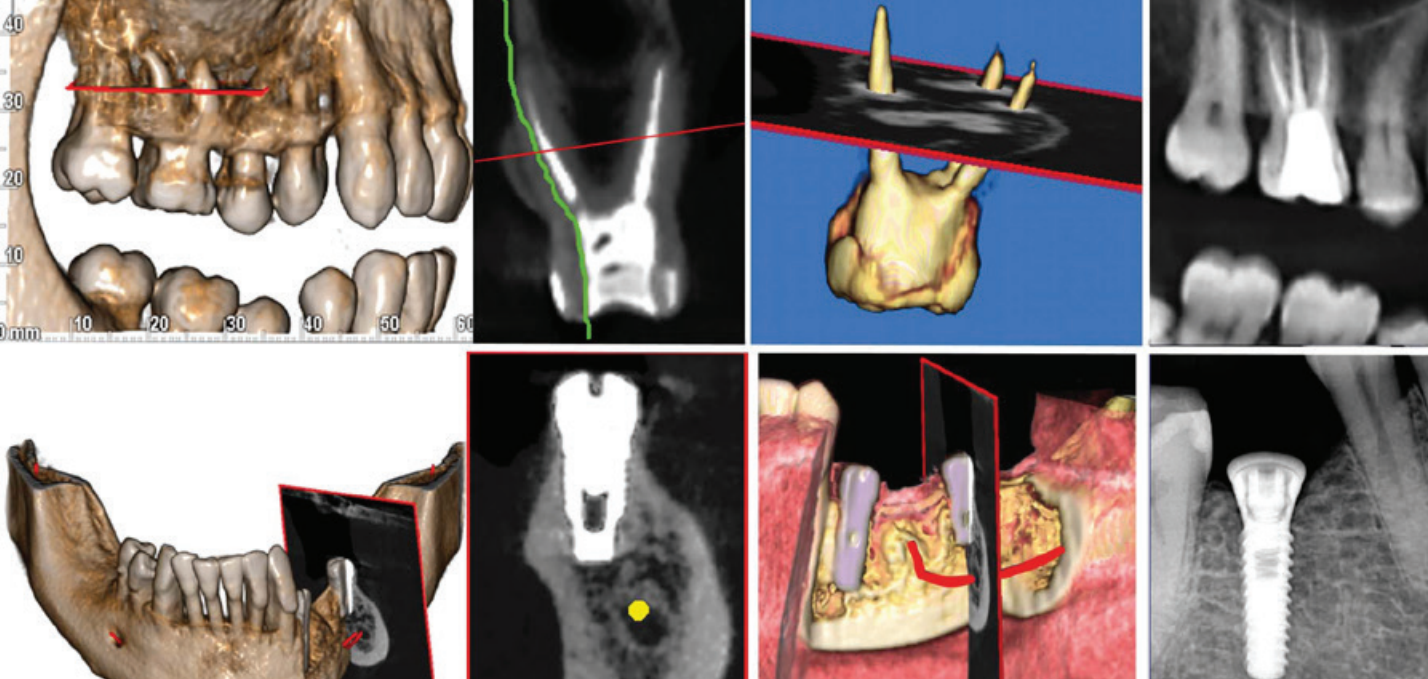

• Radyo-opak yansımaları ortadan kaldıran özellik • Doldurulmuş kanal yansımaları eleminasyonu • İmplant yansımaları eleminasyonu • Amalgam ve restorasyon yansımaları eleminasyonu

Endodontik değerlendirmeler için sadece ilgili bölgedeki ayrıntılı teşhisler yapılabilmektedir. 2D görüntülerden çok daha derinlemesine gömülü dişler arasındaki ilişkilerin neredeyse bir periapikal dozunda incelenmesi sağlar.

İmplant bölgesini çevreleyen anatomik yapılar hakkında bilgi verir. Kemik kalitesinin değerlendirmesi ve gelişmiş IRYS yazılım özelliğiyle cerrahî prosedürlerin, ameliyat sonrası iyileşme sürelerinin en iyi şekilde planlanması mümkün olur. Bu özellik sayesinde geniş kapsamlı yazılımın implant kütüphanesinde bulunan implantların seçilip konumlandırılarak görüntüler üzerinde planlama yapılabilir.